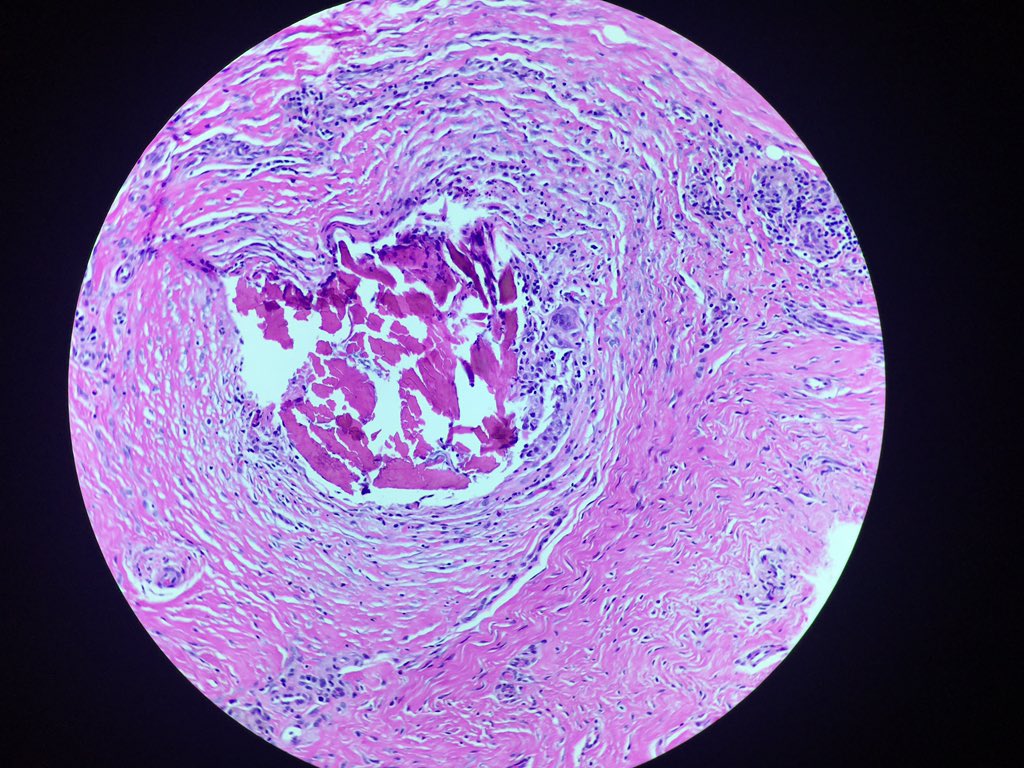

Although granulomatous vasculitis appears to occur most frequently in pulmonary sarcoidosis, it may be encountered in other conditions as well.

#pulmpath#vasculitis#granuloma pic.twitter.com/xKJh3Fxszw